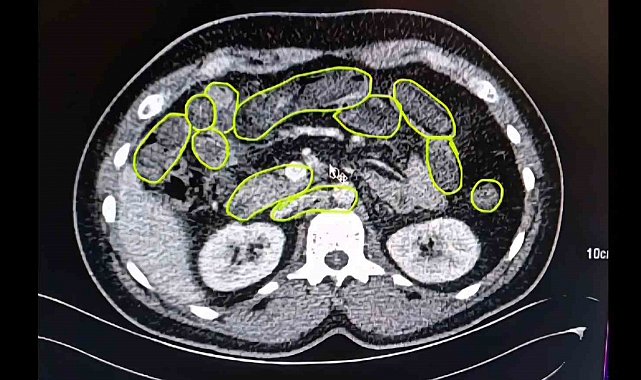

Şüphelilerin Kayseri Şehir Hastanesinde iç beden muayenesine alınırken, mide ve bağırsaklarında da çok miktarda kapsül şeklinde uyuşturucu olduğu değerlendirilen yabancı maddeler tespit edildi.